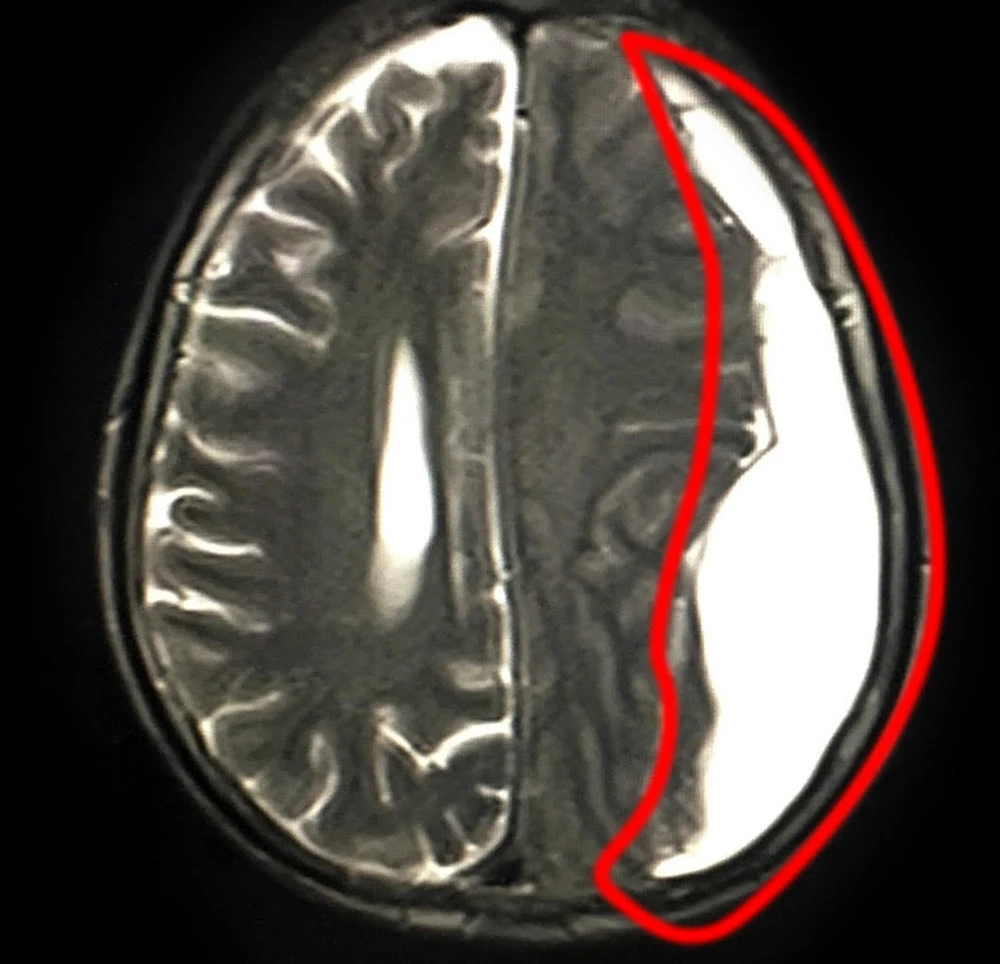

Kết quả chẩn đoán ghi nhận ông M. bị tụ máu dưới màng cứng mạn tính bán cầu trái. Ảnh: VĂN PHỤNG

Tại BV Đa khoa Xuyên Á, các bác sĩ (BS) chuyên khoa Ngoại thần kinh thăm khám và xác định ông M. bị tụ máu dưới màng cứng mạn tính bán cầu bên trái. Nếu không phẫu thuật can thiệp kịp thời thì sẽ ảnh hưởng đến tính mạng.